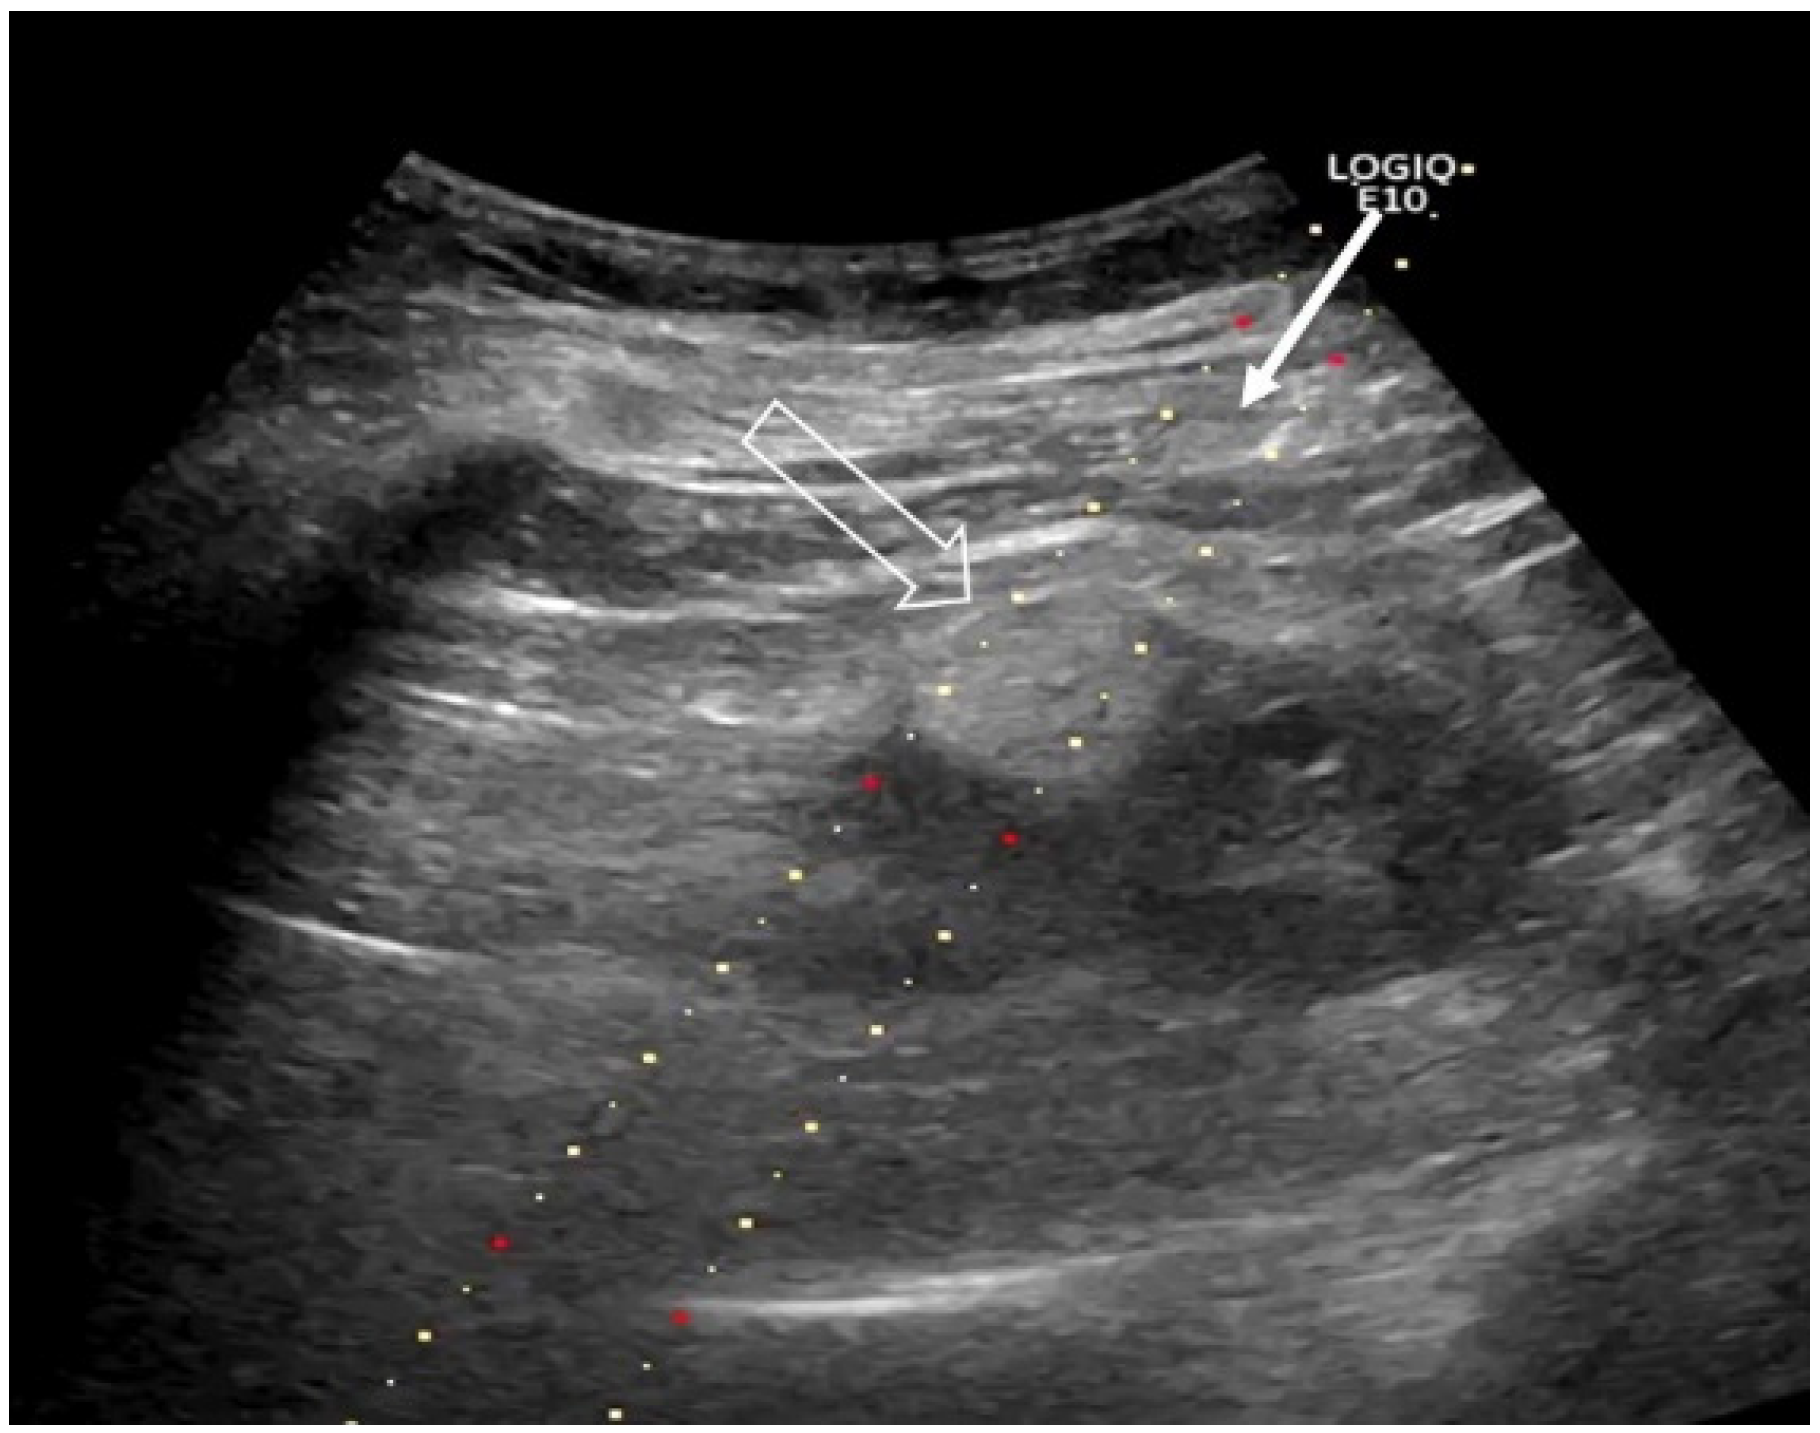

2.2. RFA—Technical Aspects